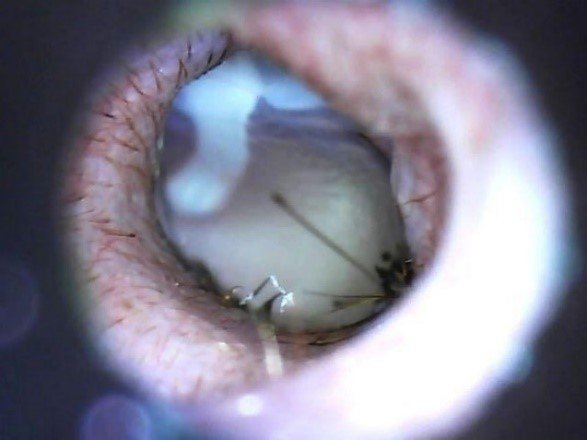

Video otoscopia

La video otoscopia è un ausilio diagnostico fondamentale nelle indagini del canale auricolare in corso di otiti e corpi estranei. Tramite questo strumento si rende possibile l’asportazione di materiale patologico all’interno dell’orecchio e l’esame completo del canale auricolare e del timpano. La tecnica viene eseguita in anestesia generale per ottenere il miglior risultato senza dolore per il paziente

Lavaggio auricolare in otoscopia per otite cronica

Orecchio dopo lavaggio

Timpano e orecchio in condizioni fisiologiche